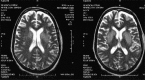

Dyselectrolytemia, especially hyponatremia is a common occurrence in hospitalized patients, and a number of dreaded complications arise out of the disorder itself and its treatment. Osmotic demyelination syndrome develops secondary to rapid correction of hyponatremia. As the disease is rare and available literature from Intensive Care Units are limited, we report our retrospective observation over 5 years. Overall incidence was 2.5% with altered sensorium and hypokalemia as most common symptom and associated factor respectively. Isolated pontine involvement was in 41% and combined pontine, and extra-pontine lesions were found in 23% of cases. All patients received supportive therapy; out of which 2 died and complete neurological recovery was seen in 24% of patients. Our findings suggest that a well organized supportive therapy and multidisciplinary approach is of more concern than many available therapeutic modalities which are still to be proved.